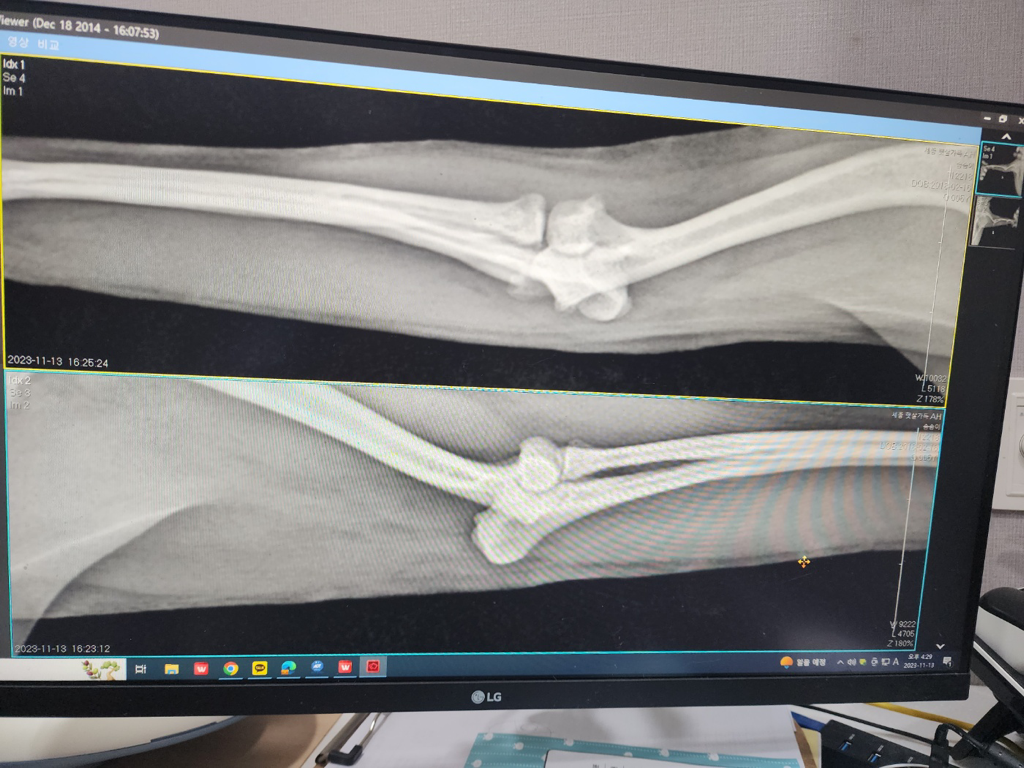

위 사진이 문제가 되는 다리입니다 강아지가 오른쪽 앞발을 들고만있고 디디지를 못하고 자꾸 절어서 병원에갔더니 뼈가 용해된건지 염증인지 골절인지 잘 모르겠다고 큰병원가보라고 하는데 이거 골육종인가요??골육종이라면 전이 가능성이 큰가요??ㅜㅜ내일 병원 갈거긴 한데 너무 걱정됩니다 ㅜㅜ 식욕은 있는편이예요

다리를 딛지 못해서 그런 증상이 나타나는 경우 조직검사와 CT촬영을 해보셔야 정확할듯 합니다.

방사선 만으로는 확진을 드리기가 어렵네요

사진상 해상도의 문제로 정확한 소견을 알려드릴 수 없고 수의사가 소견을 어떻게 썻는지 모르겠지만, 병변의 변연이나 테두리가 지저분하거나 예쁘지 않은 경우는 많은 경우 결과가 좋지 못한 것으로 알고 있습니다.

뼈의 국소적 융해는 종양과 감염성 염증 둘중 하나인 경우가 대부분이나 감염성 염증은 물림 사고 등의 창상이 없는경우 일어나기 어려워

국소적인 골 융해가 보이면 골종양의 가능성이 매우 높은것으로 여깁니다.

하지만 확진을 위해서는 세포학 검사가 필수적으로 필요하니 동물병원에 가셔서 검진 잘 받으시고 진단 후 원인에 따른 치료를 받으시기 바랍니다.

외관상으로는 골육종 같지는 않습니다 통증이 있는 경우는 골육종 보다는 염증일 가능성이 있습니다. 염증을 일으키는 원인은 사진상으로는 정확히는 알 수 없습니다.